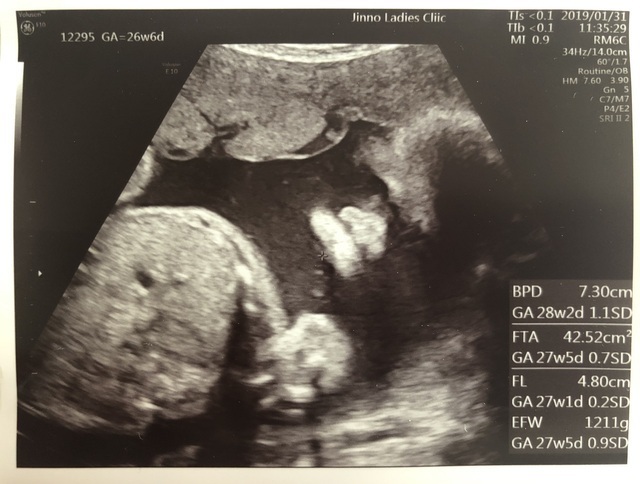

26週2日(26w2d・女の子)|るる. さん(28歳)

エコー写真撮影時のエピソード:

この頃は、ちょうど赤ちゃんの性別が分かった時でした。もちろんどちらでも嬉しいものの、やはり性別がわかると買い物の楽しみも倍増、名前も考え始められるとあって、家族もより喜んでくれました。

ちなみに、この頃は胎動が一層激しくなっていった時期でもあり、仕事中でも存在を感じては温かい気持ちになりました。